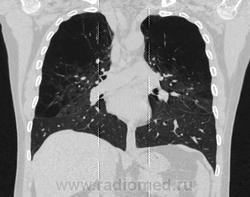

Заранее прошу прощение за некачественные рентгенограммы, так как фотографировал с пленки на телефон. А на КТ-исследовании артефакты, так как, как раз перед обследованием данного больного произошел выход из строя какой то платы.

назначен день КТ, как я уже говорил прям пред обследованием пациента полетела какая то плата, появились артефакты, но явность картины не скрыть!):

написали панлобулярная эмфизема преимущественно в верхних долях. мне кажется это  говорит о врожденной верхнедолевой эмфиземе

Похоже, что мало сосудов для просто эмфиземы, практически все сосуды вверху исходят из средних отделов.  Нет ли пороков развития сосудов легких, хорошо бы контрастирование или узи сердца.

Чисто субективно корни представляются гипопластичными в области головок и частично тел.